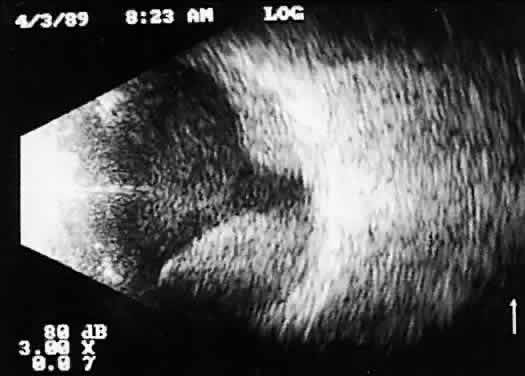

Tumors with great acoustic heterogeneity, such as choroidal hemangiomas, where adjoining cell and tissue layers have marked differences in acoustic impedance, create large echo amplitudes at each interface. These tumor types have typical high internal reflections at each major interface. These high internal reflections make the lesions appear solid white in B-scan displays and produce highamplitude spikes during A-scan imaging (Fig. 12).

Fig. 12. Contact B-scan and simultaneous A-scan: choroidal hemangioma. Ultrasonically heterogeneous tissue shows strong reflectivity at all levels, appearing white in B-scan gray scale.